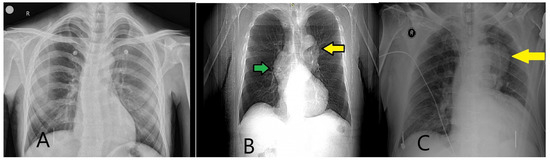

5.2.1. X-Ray and Electrocardiography

- Song, D.H.; Choi, J.H.; Lee, J.Y. Predicting acute aortic syndrome using aortic dissection detection risk score, D-dimer, and X-ray. Heliyon 2023, 9, e20578. [Google Scholar] [CrossRef]

- Morello, F.; Santoro, M.; Fargion, A.T.; Grifoni, S.; Nazerian, P. Diagnosis and management of acute aortic syndromes in the emergency department. Intern. Emerg. Med. 2021, 16, 171–181. [Google Scholar] [CrossRef] [PubMed]

- Nazerian, P.; Pivetta, E.; Veglia, S.; Cavigli, E.; Mueller, C.; de Matos Soeiro, A.; Leidel, B.A.; Lupia, E.; Rutigliano, C.; Wussler, D.; et al. ADvISED Investigators. Integrated Use of Conventional Chest Radiography Cannot Rule Out Acute Aortic Syndromes in Emergency Department Patients at Low Clinical Probability. Acad. Emerg. Med. 2019, 26, 1255–1265. [Google Scholar] [CrossRef] [PubMed]